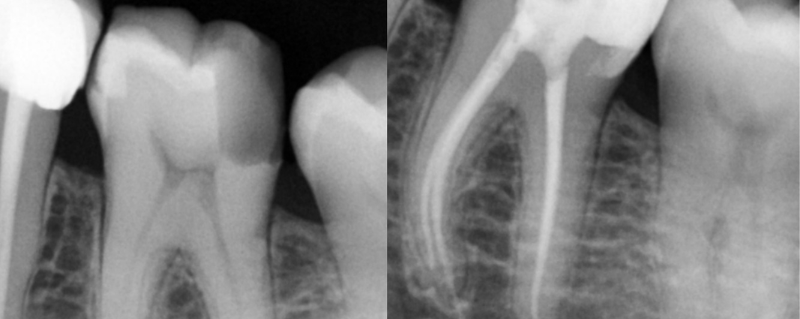

- Digital X-rays for accurate diagnosis

A root canal is needed when the inner part of a tooth (called the pulp) becomes infected due to deep decay, cracks, or injury. During the procedure, the infected tissue is removed, the inside of the tooth is carefully cleaned and disinfected, and then sealed to prevent future infection.

The tooth is later protected with a filling or crown, allowing it to function like a natural tooth again—without pain.